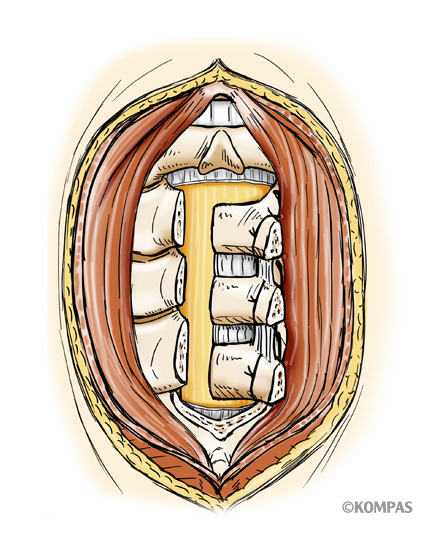

腰椎棘突起縦割式椎弓切除術

適応となる疾患:腰部脊柱管狭窄症、腰椎変性すべり症など

腰椎後方(背中)から椎弓、肥厚した黄色靭帯を切除し、硬膜管(馬尾神経の通っている管)の圧迫を解除します。棘突起を縦割することで腰背筋を骨から切離せず温存して、余分な組織のみ切除する低侵襲な手術を行います。従来の手術に比べ、術後の腰痛が軽度です。手術時間は1時間くらいで翌日から歩行が許可されます。入院期間は通常10~14日ぐらいになります。